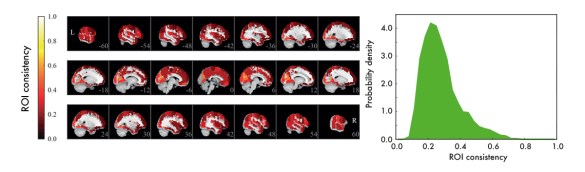

We used resting-state data – data recorded with subjects who are just resting in the scanner, instructed to do nothing – to construct functional ROI-level networks based on some available atlases. We defined a measure of ROI consistency that has a value of one if all the voxels that make up the ROI have identical time series (making the ROI functionally homogeneous, which is good), and a value of zero if the voxels do not correlate at all (making that ROI a bad idea, in general).

[Figure from our paper in Network Neuroscience]

We found that consistency varied broadly between ROIs. While a few ROIs were quite consistent (values around 0.6), many were not (values around 0.2). There were many low-consistency ROIs in three commonly used brain atlases.